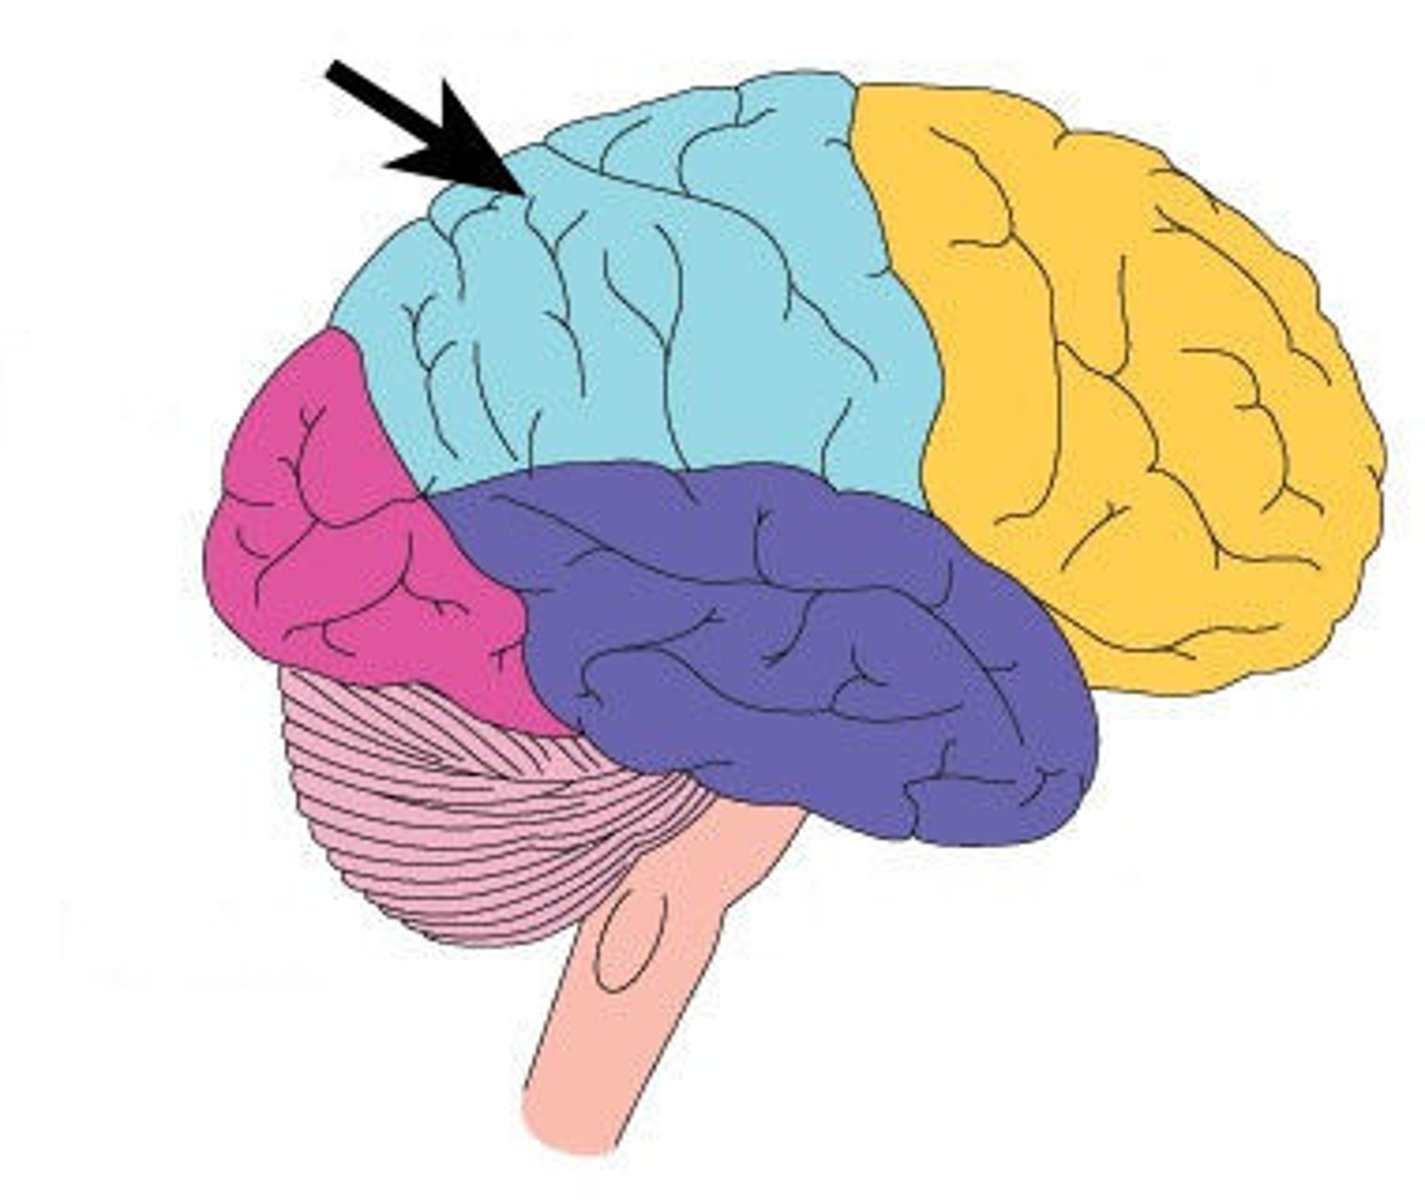

central sulcus

frontal lobe

parietal lobe

temporal lobe

occipital lobe